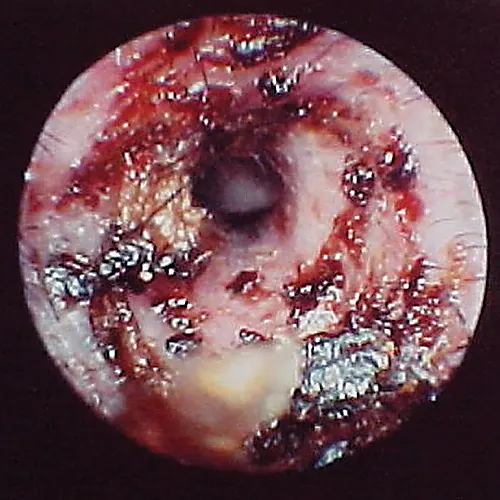

Damage to the tympanic membrane caused by trauma (eg, chewing activity of ear mites, previously ruptured eardrum that has healed) or chronic infection disturbs this epithelial migration process. When epithelial migration is slowed, as with age or from disease, debris, cerumen, and hairs accumulate on the eardrum. A ceruminolith may develop on the eardrum on the external ear canal side (Figure 14). These plugs may also consist of dried mucus or medication that has hardened in the horizontal canal.

Globoid brown-to-black mass occluding internal ear canal.

FIGURE 14

Wax plug (ceruminolith) on the eardrum

Wax plug in an ear. Accumulations of wax (cerumenolith) commonly  show up at the eardrum when the eardrum epithelial surface has been previously compromised.  Dried oily medication and inspissated mucus from the bulla can look similar.

Cerumen accumulation against the eardrum, in addition to stenosis and hyperplasia, can impede conduction of sound waves and result in temporary hearing loss. Ceruminoliths require mechanic removal, preferably with endoscopic grasping forceps through a video otoscope with the patient anesthetized. If the eardrum is not intact, exudates such as mucus and pus can leak into the horizontal canal and inspissate at the eardrum. This condition can look like a ceruminolith. The mucoid secretions dissolve in water and can be removed with a water or saline flush of the horizontal canal.